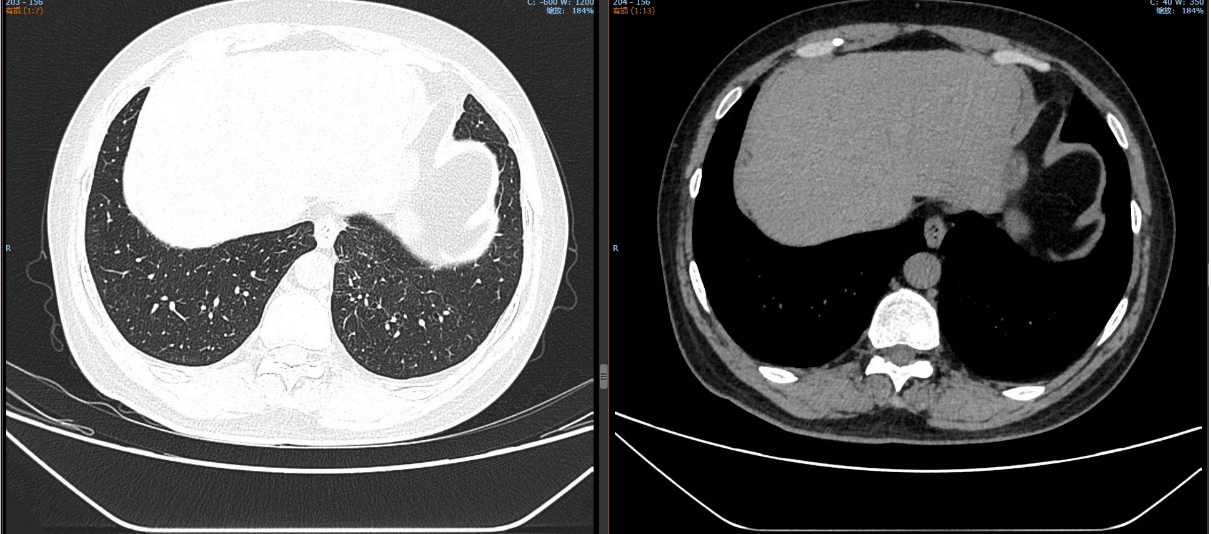

治疗5个月后(2025-05-07):复查CT显示左肺病灶显著缩小,达到PR,肺内结节明显吸收。

截至目前,PFS已超过10个月,病情持续稳定。